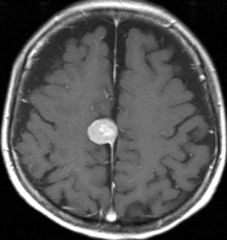

典型的な髄膜腫

この髄膜腫は中程度の大きさのものです。円蓋部髄膜種という最も多い最も手術の簡単なタイプです。麻痺や失語症やてんかんなどの症状はありません。とても美しくて若い女性の髄膜腫でしたが,子供に遺伝はしませんし,癌などと違ってタバコなどこれといった原因がなくて発生するものです。

MRIでの髄膜腫の見え方は撮影の仕方によっていろいろです。左からT1強調画像,T2強調画像,フレア画像といいます。腫瘍の横に小さく白い領域がありますが,これは脳の腫れた部分で脳浮腫といいます。髄膜腫があると周囲に脳浮腫が生じることがあります。

最も見やすいのが,ガドリニウム造影剤を注射して撮影するものです。一般的に髄膜腫は造影剤で白く映し出されます。この腫瘍は左脳側にあります。MRIの軸面という輪切りの写真では左右が逆になりますから注意してください。脳を下から見た図になっています。MRIはいろいろな方向から腫瘍を見ることができますが,右は冠状断という正面から見た図です。よく見ると腫瘍の上と下のはじっこに線状に糸を引いたように造影される部分があります。これをテールサイン(しっぽのサイン)といいます。腫瘍が硬膜に沿って延びている可能性があることを示しています。

手術後のMRIです。腫瘍は全部取れていて後遺症もありません。圧迫されて変形していた脳はきれいに元に戻っていますし脳浮腫も消えました。一般的に若い人の脳ほどきれいに元に戻ります。注意しなければならないのは,少しでも取り残した場合には,何年か後に10%-20%くらいで再発があることです。もちろん完全に取れた時の再発はほとんどありません。